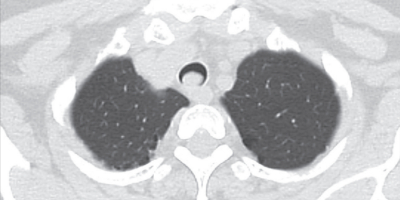

体温 36.8 ℃。血圧 118/64 mmHg。呼吸数 24/分。SpO₂ 94 %(room air)。胸部単純 CTを別に示す。

この患者で聴取される呼吸音として最も可能性が高いのはどれか。

d. fine crackles